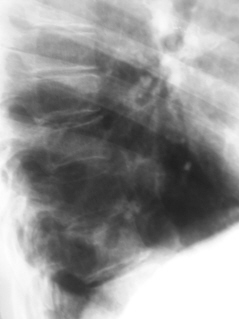

Иллюстрация 6. Рентгенограмма в прямой проекции.

Иллюстрации 7, 8, 9 – фрагменты рентгенограммы с увеличением. Справа медио-базально определяется полостное образование с довольно «толстой» стенкой, с нечётким наружным контуром. В окружающей ткани «очаги отсева» не определяются. Рисунок правого корня в области хвоста незначительно усилен, обогащен, тень его структурна.